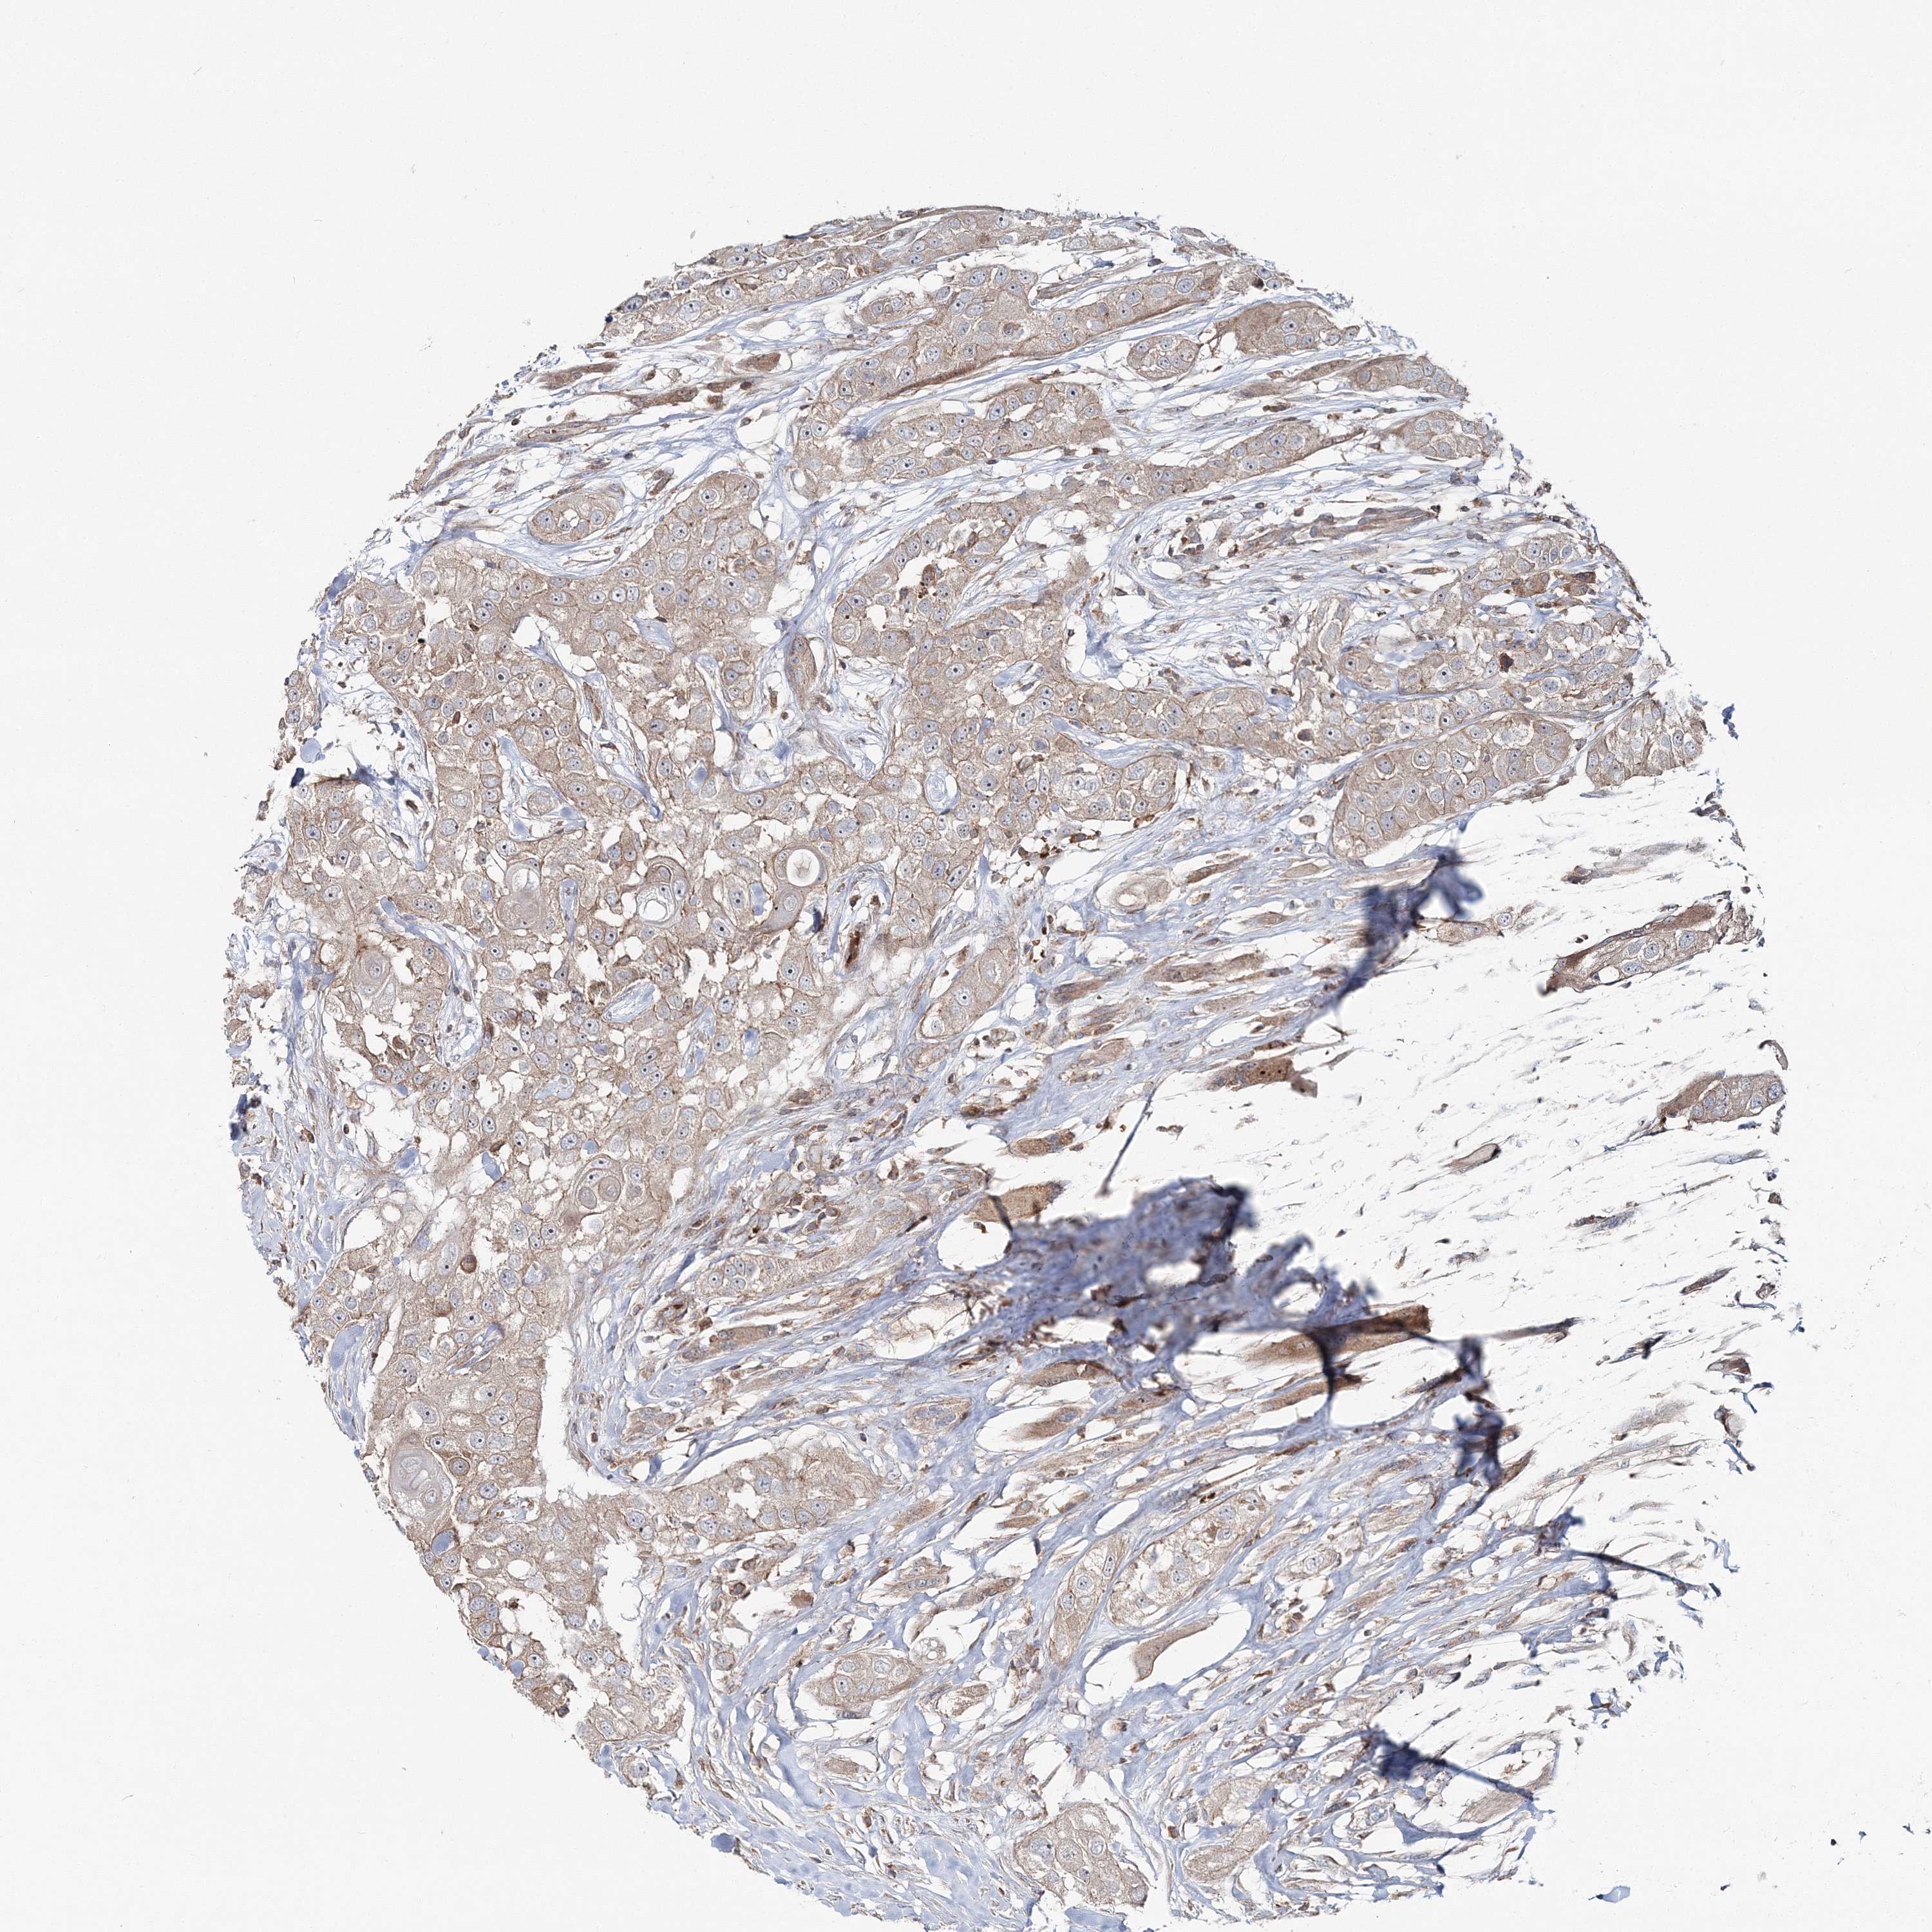

HEAD AND NECK CANCER - Protein expressioni

A mouse-over function shows sample information and annotation data. Click on an image to view it in a full screen mode. Samples can be filtered based on level of antibody staining by selecting one or several of the following categories: high, medium, low and not detected. The assay and annotation is described here.

Note that samples used for immunohistochemistry by the Human Protein Atlas do not correspond to samples in the TCGA dataset.

Antibody stainingi

Antibody staining in the annotated cell types in the current human tissue is reported as not detected, low, medium, or high, based on conventional immunohistochemistry profiling in selected tissues. This score is based on the combination of the staining intensity and fraction of stained cells.

Each image is clickable and will lead to virtual microscopy that enables deeper exploration of all samples and also displays staining intensity scores, fraction scores and subcellular localization as well as patient and tissue information for each sample.

Antibody HPA036428

Staining

High

Medium

Low

Not detected

Intensity

Strong

Moderate

Weak

Negative

Quantity

>75%

75%-25%

<25%

None

Location

Nuclear

Cytoplasmic/membranous

Cytoplasmic/membranous,nuclear

Squamous cell carcinoma, NOS

Squamous cell carcinoma, metastatic, NOS